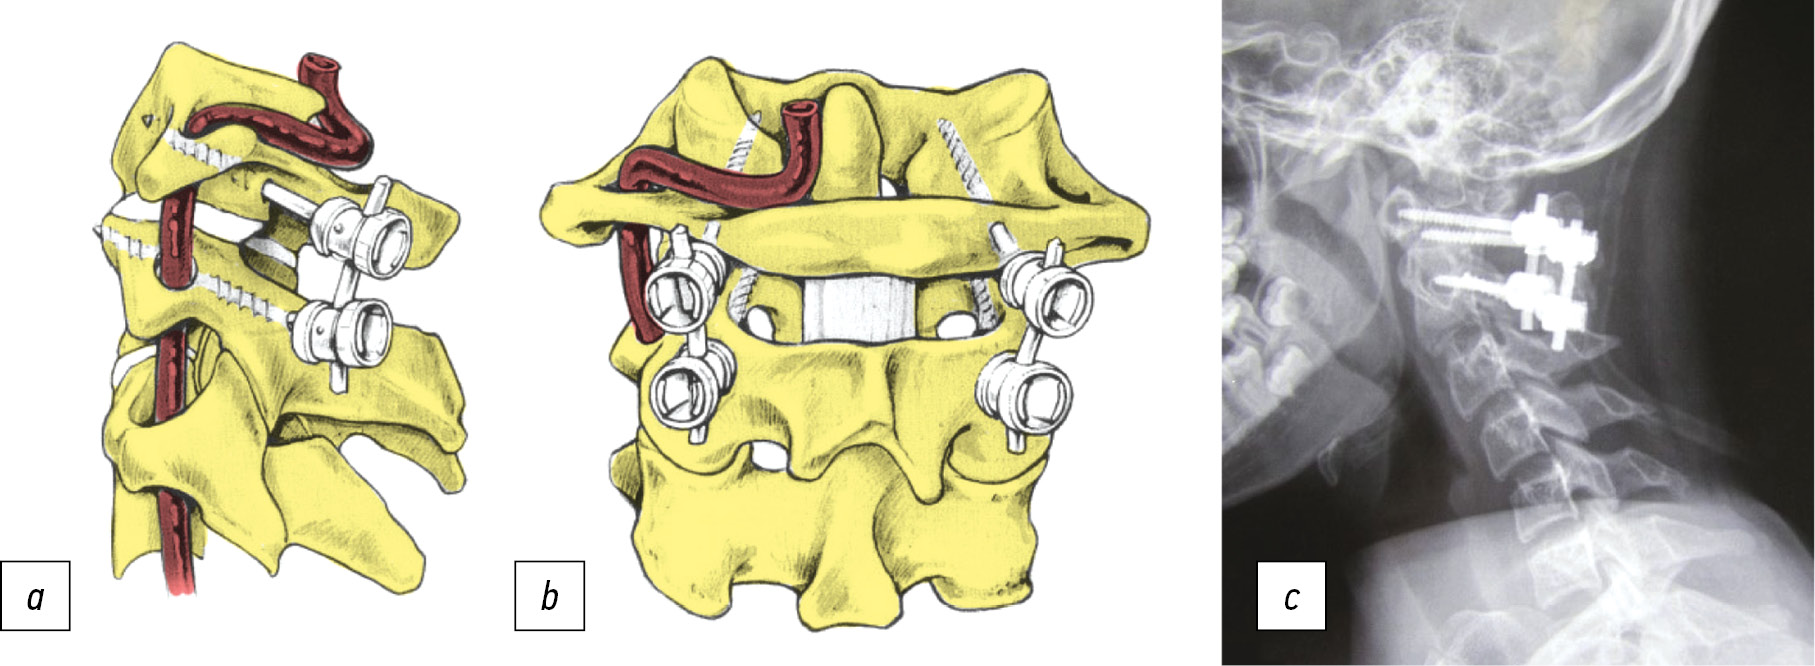

A. Goel с соавт. в 1994 г. были первыми, кто описал применение независимых CI и CII винтов, соединённых пластиной. В опубликованном ими исследовании с участием 160 пациентов самая большая группа (48 пациентов) имела зубовидную кость, при использовании этой техники отмечались хорошие результаты [23, 24] (рис. 2).

Рис. 2. Методика фиксации СI-СII по Goel. a — иллюстрация методики, b — рентгенограмма в боковой проекции.

Fig. 2. C1-C2 Goel fixation techniques. a — illustration of technique, b — the X-ray in lateral view.

J. Harms, R.P. Melcher в 2001 г. описали методику фиксации СI-СII сегмента с проведением полиаксиальных винтов через боковые массы СI и через pars interarticularis транспедикулярно в СII с последующим выполнением корригирующего манёвра под рентген-контролем и фиксацией стержнями (рис. 3) [25]. Шесть из 37 пациентов, описанных в исследовании, имели зубовидную кость. В позднем послеоперационном периоде у всех пациентов наблюдались рентгенологические признаки спондилодеза. Эта техника имеет значительные преимущества: корригирующий манёвр может быть выполнен интраоперационно, и риск повреждения позвоночной артерии значительно снижен [25].

Рис. 3. Методика фиксации СI-СII по Harms и Melcher. a — вид сбоку, b — вид сзади, с — рентгенограмма в боковой проекции.

Fig. 3. C1-C2 Harms and Melcher fixation technique. a — side view, b — back view, с — the X-ray in lateral view.